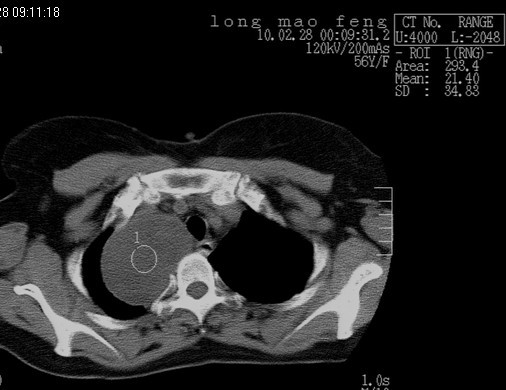

以下是引用随光逐影在2010-3-1 8:36:00的发言:[br]右上纵隔囊性占位性病变,考虑支气管囊肿,不排除神经源性肿瘤。